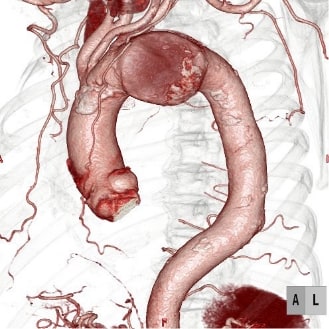

ステントグラフト挿入前CT

ステントグラフト挿入後CT

大動脈手術では、このシステムを利用して積極的に低侵襲治療である血管内治療(ステントグラフト内挿術)を行っています。腹部大動脈瘤だけではなく、弓部に至る胸部大動脈瘤でも、外科的処置を併用したステントグラフト治療を行なっております。